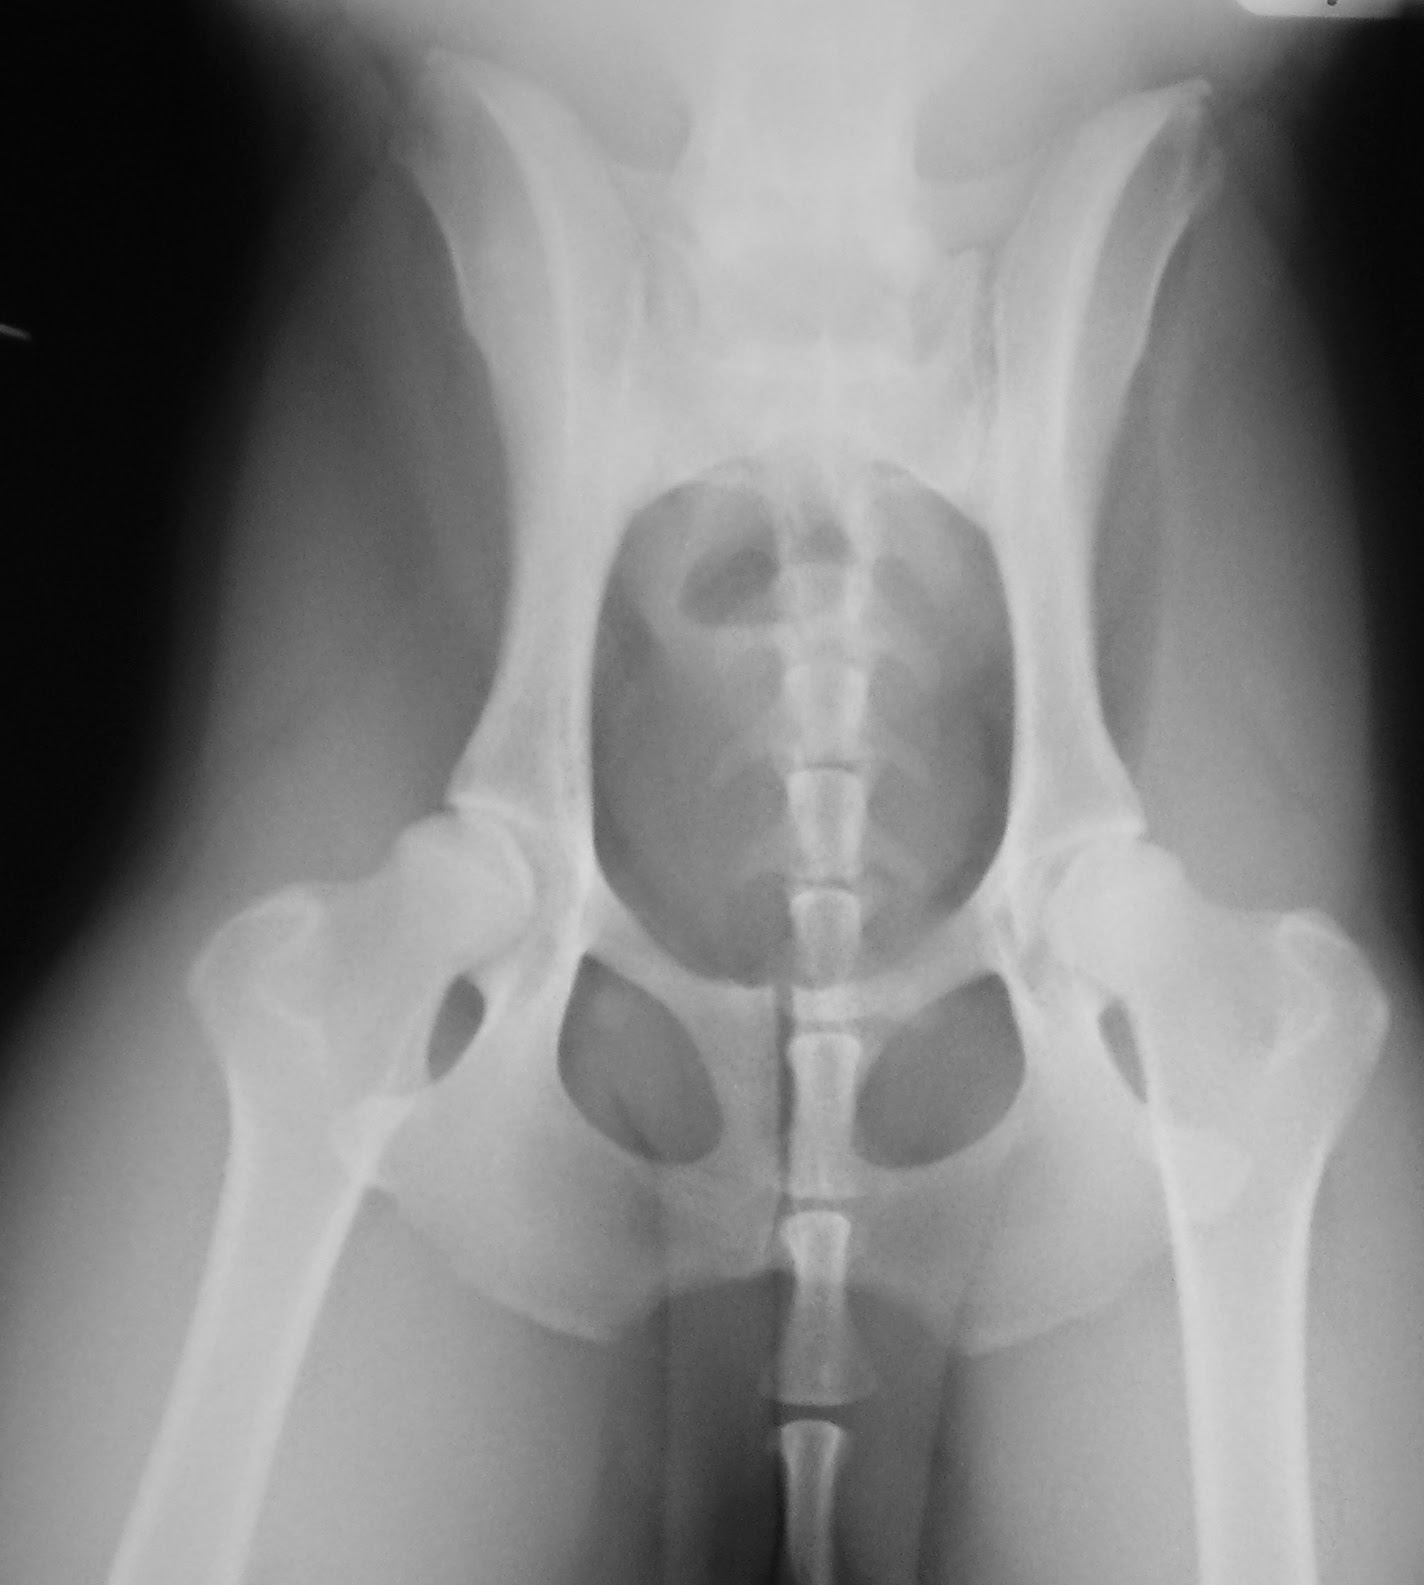

Το εξάρθρημα του ισχίου ανατάχθηκε συντηρητικώς υπό γενική αναισθησία αμέσως μετά την επιβεβαίωση της διάγνωσης και η ανάταξη ελέγχθηκε με ακτινογράφηση (Εικ. 3). Η άρθρωση του ισχίου ακινητοποιήθηκε με επίδεσμο Ehmer

Εικ. 3: ΄Υπτια ακτινογραφία πυέλου μετά την ανάταξη του εξαρθρήματος του ισχίου